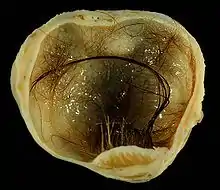

A dermoid cyst is a teratoma of a cystic nature that contains an array of developmentally mature, solid tissues. It frequently consists of skin, hair follicles, and sweat glands, while other commonly found components include clumps of long hair, pockets of sebum, blood, fat, bone, nail, teeth, eyes, cartilage, and thyroid tissue.

As dermoid cysts grow slowly and contain mature tissue, this type of cystic teratoma is nearly always benign. In those rare cases wherein the dermoid cyst is malignant, a squamous cell carcinoma usually develops in adults, while infants and children usually present with an endodermal sinus tumor.[1]:781